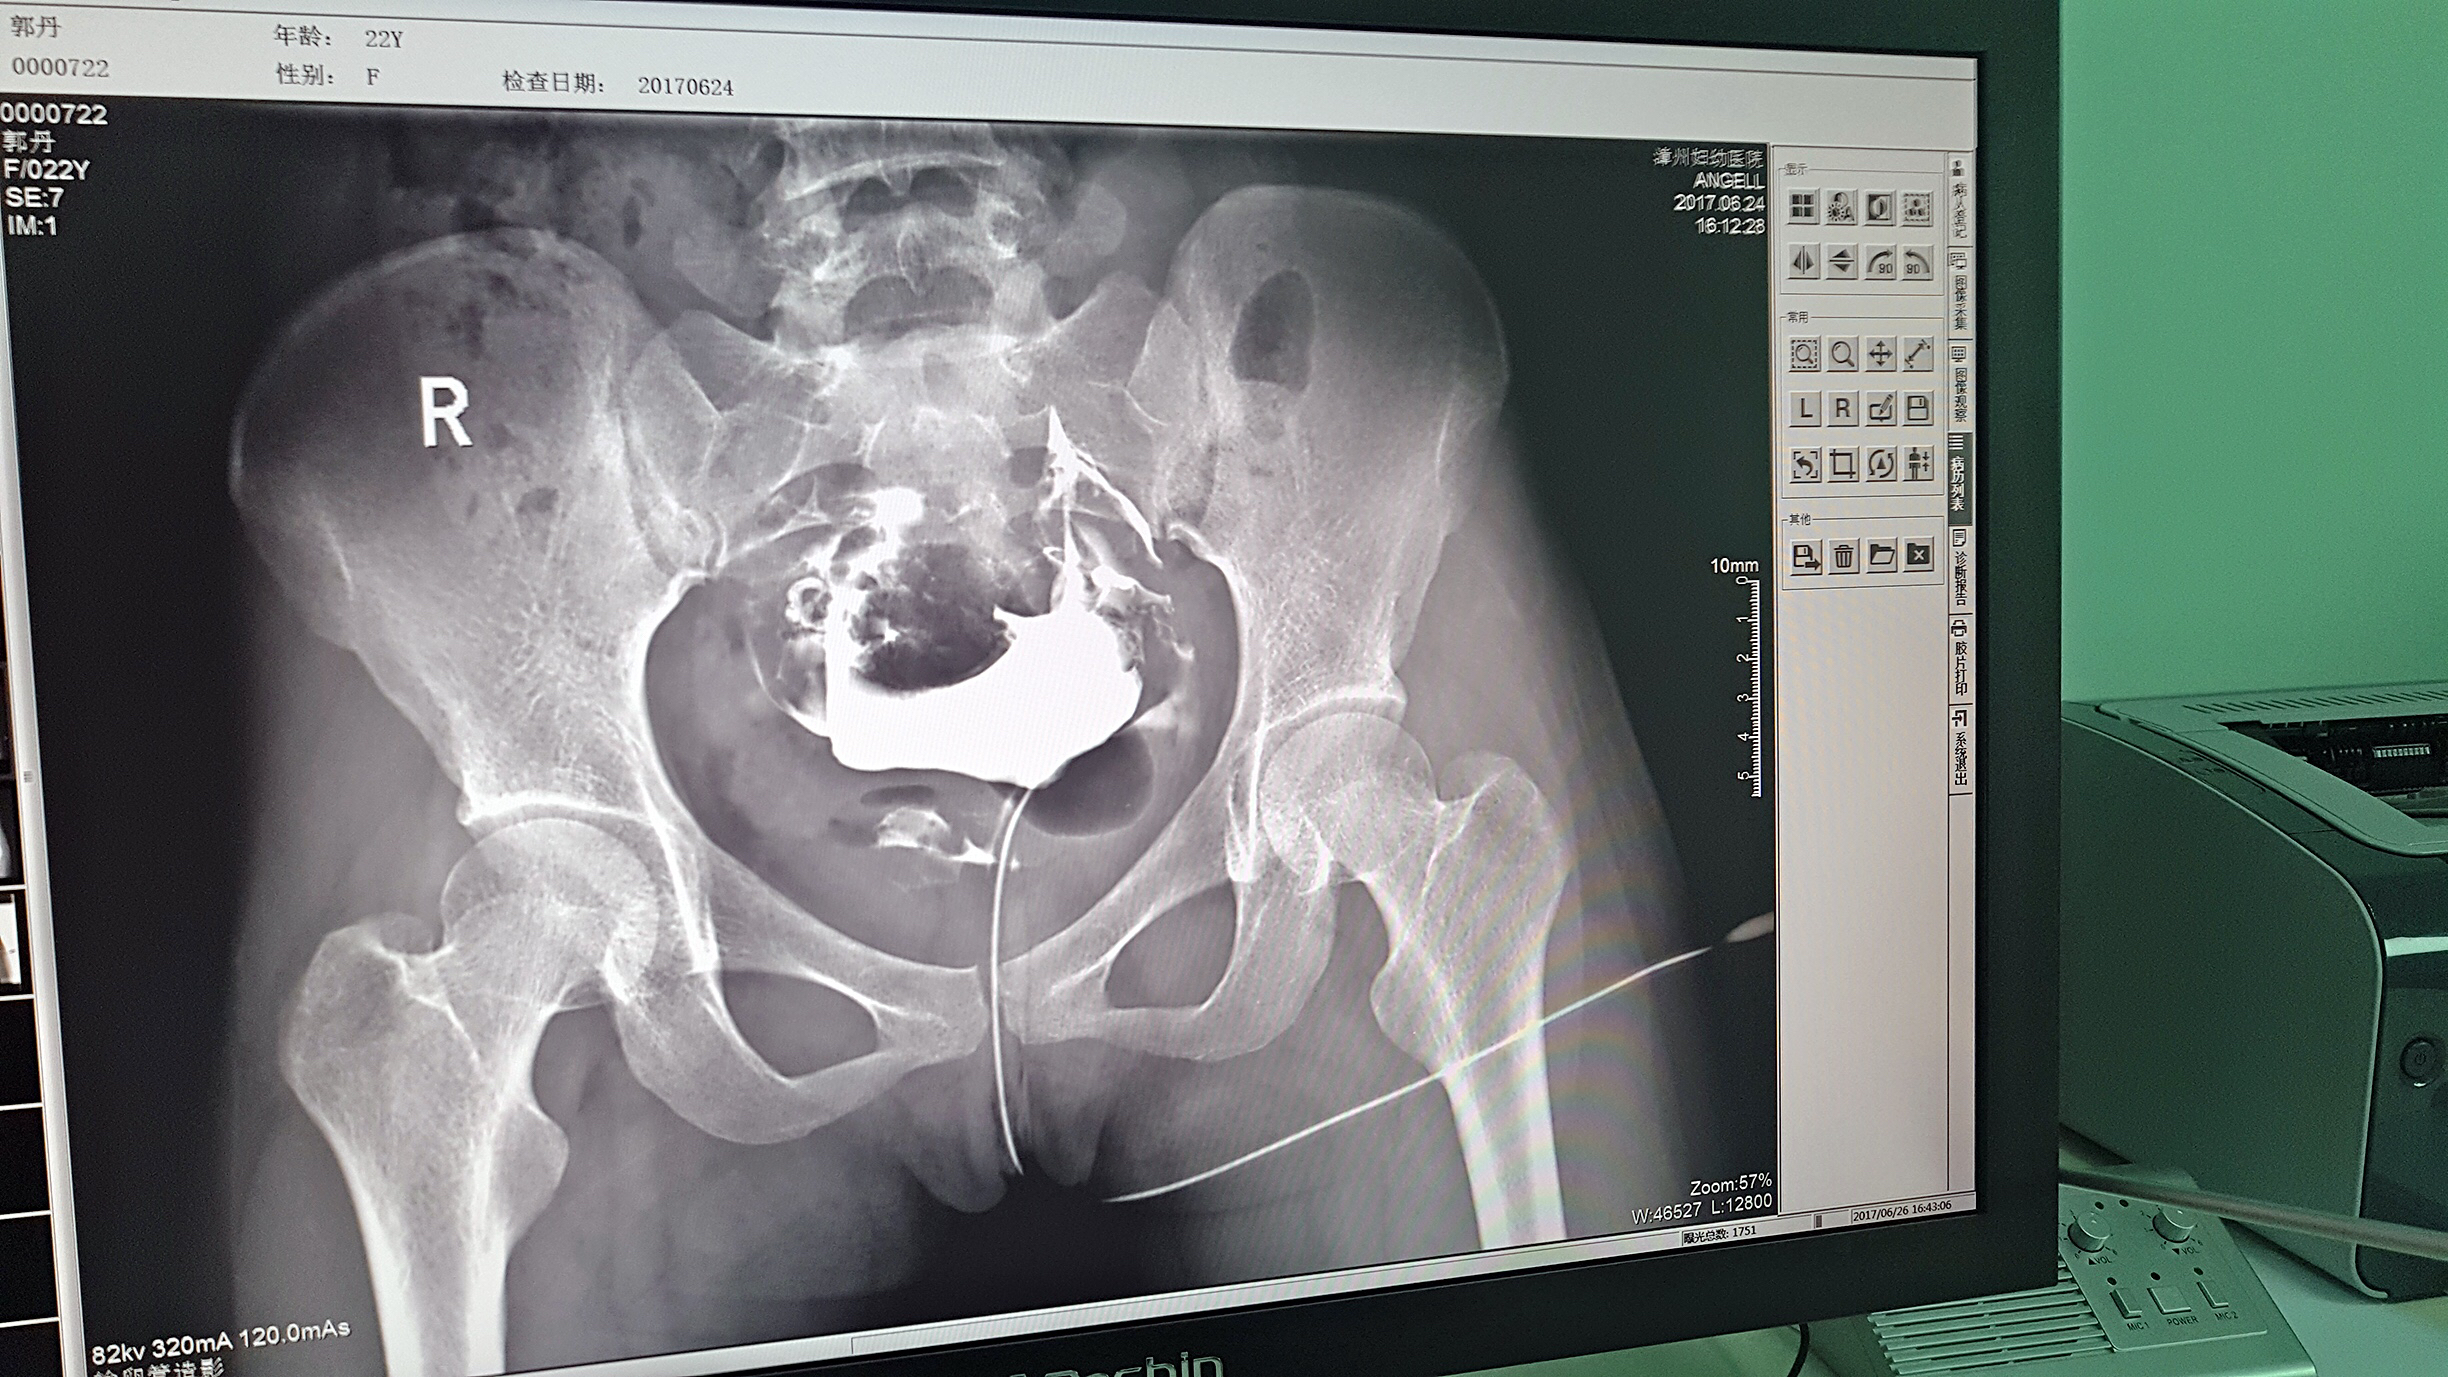

但是这家医院一直面临一个问题,妇科中输卵管检查无法完成。因为其使用的是静态DR,无法做输卵管造影检查,患者不得不前往其他医院继续检查,使得医院留不住患者,造成一笔损失。久而久之,患者可能为了图方便,直接去了其他医院治疗,这对医院经营的影响是巨大的。

2016年,漳州妇幼医院几经对比、筛选,最终选择了ty8天游平台登录科技的动态DR产品。它选择ty8天游平台登录科技动态DR产品的原因很简单,动态DR不仅具备普通DR的功能,还能做输卵管造影,成像质量高以及设备性价比高。

目前设备除了用于常规拍片之外,主要用于输卵管造影检查,平均每个月有超过20个患者在漳州妇幼医院做输卵管造影检查。在此之前,漳州市只有市医院、175解放军区医院等大三甲医院才能做输卵管造影检查,这不仅让三甲医院人满为患,而且下级医院却因为不能做某项检查而造成资源浪费。因为有了设备,漳州妇幼医院可以满足患者的一些特殊检查需求,已经有很多患者慕名而来。

漳州妇幼医院放射科的陈主任日常跟这台设备打交道是最多的,他最有发言权。在ty8天游平台登录科技的回访中,陈主任说:这台设备具备先进的诊断功能,操作方便,能够拍摄出清晰的影片,进而对患者病情能够实现精准诊断。同时在医院对患者诊断能力方面有较大提升,留住了大量患者,为患者提供了更好的医疗服务。